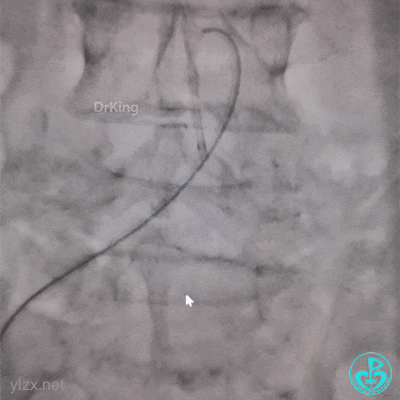

带的J-W转,突然血压没了,看下面,悲剧了。

糟糕,打折了,想解开,重新换管子。

结果上面又出问题。

管子反折,J-W根本无法通过。